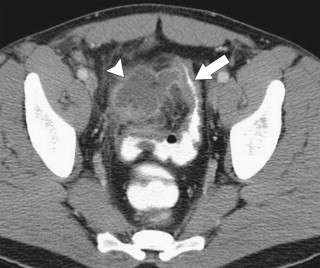

The findings are most often visualized by CT, particularly because patients are often serially imaged to evaluate for any local cancer recurrence or metastatic disease, although MRI often detects more subtle changes ( Fig. 5-40 ). Associated inflammatory changes are often observed in the surrounding mesentery (fat-stranding). This is commonly seen in the presacral region after radiation for rectal cancer preceding attempted surgical removal of the tumor. Radiation changes can sometimes be difficult to differentiate from local recurrence, but awareness that the patient has undergone radiation should alert the radiologist that the changes are benign rather than malignant recurrence. Increasingly, PET imaging is used to differentiate postradiation changes from recurrent disease ( Fig. 5-41 ).

Figure 5-41, Axial CT ( A ) and PET ( B ) in a 73-year-old man with prior colectomy for rectal cancer and question of postoperative pelvic changes versus recurrence. PET imaging confirms tumor recurrence ( arrows ).